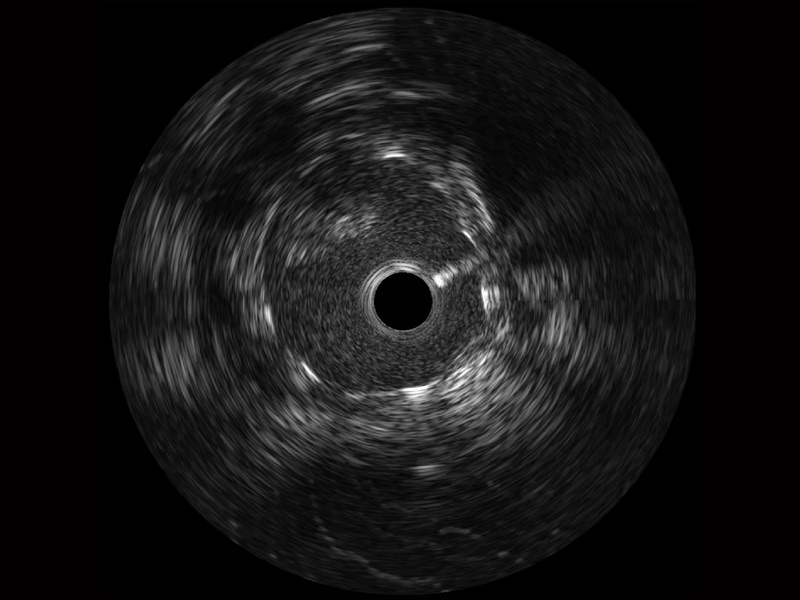

百老汇电子游戏官网宽频IVUS图像

对比传统IVUS导管成像,百老汇电子游戏官网宽频IVUS图像的近场支架梁显影更细腻,远场中膜外血管仍清晰可辨,兼顾远中近,兼顾分辨力与穿透深度